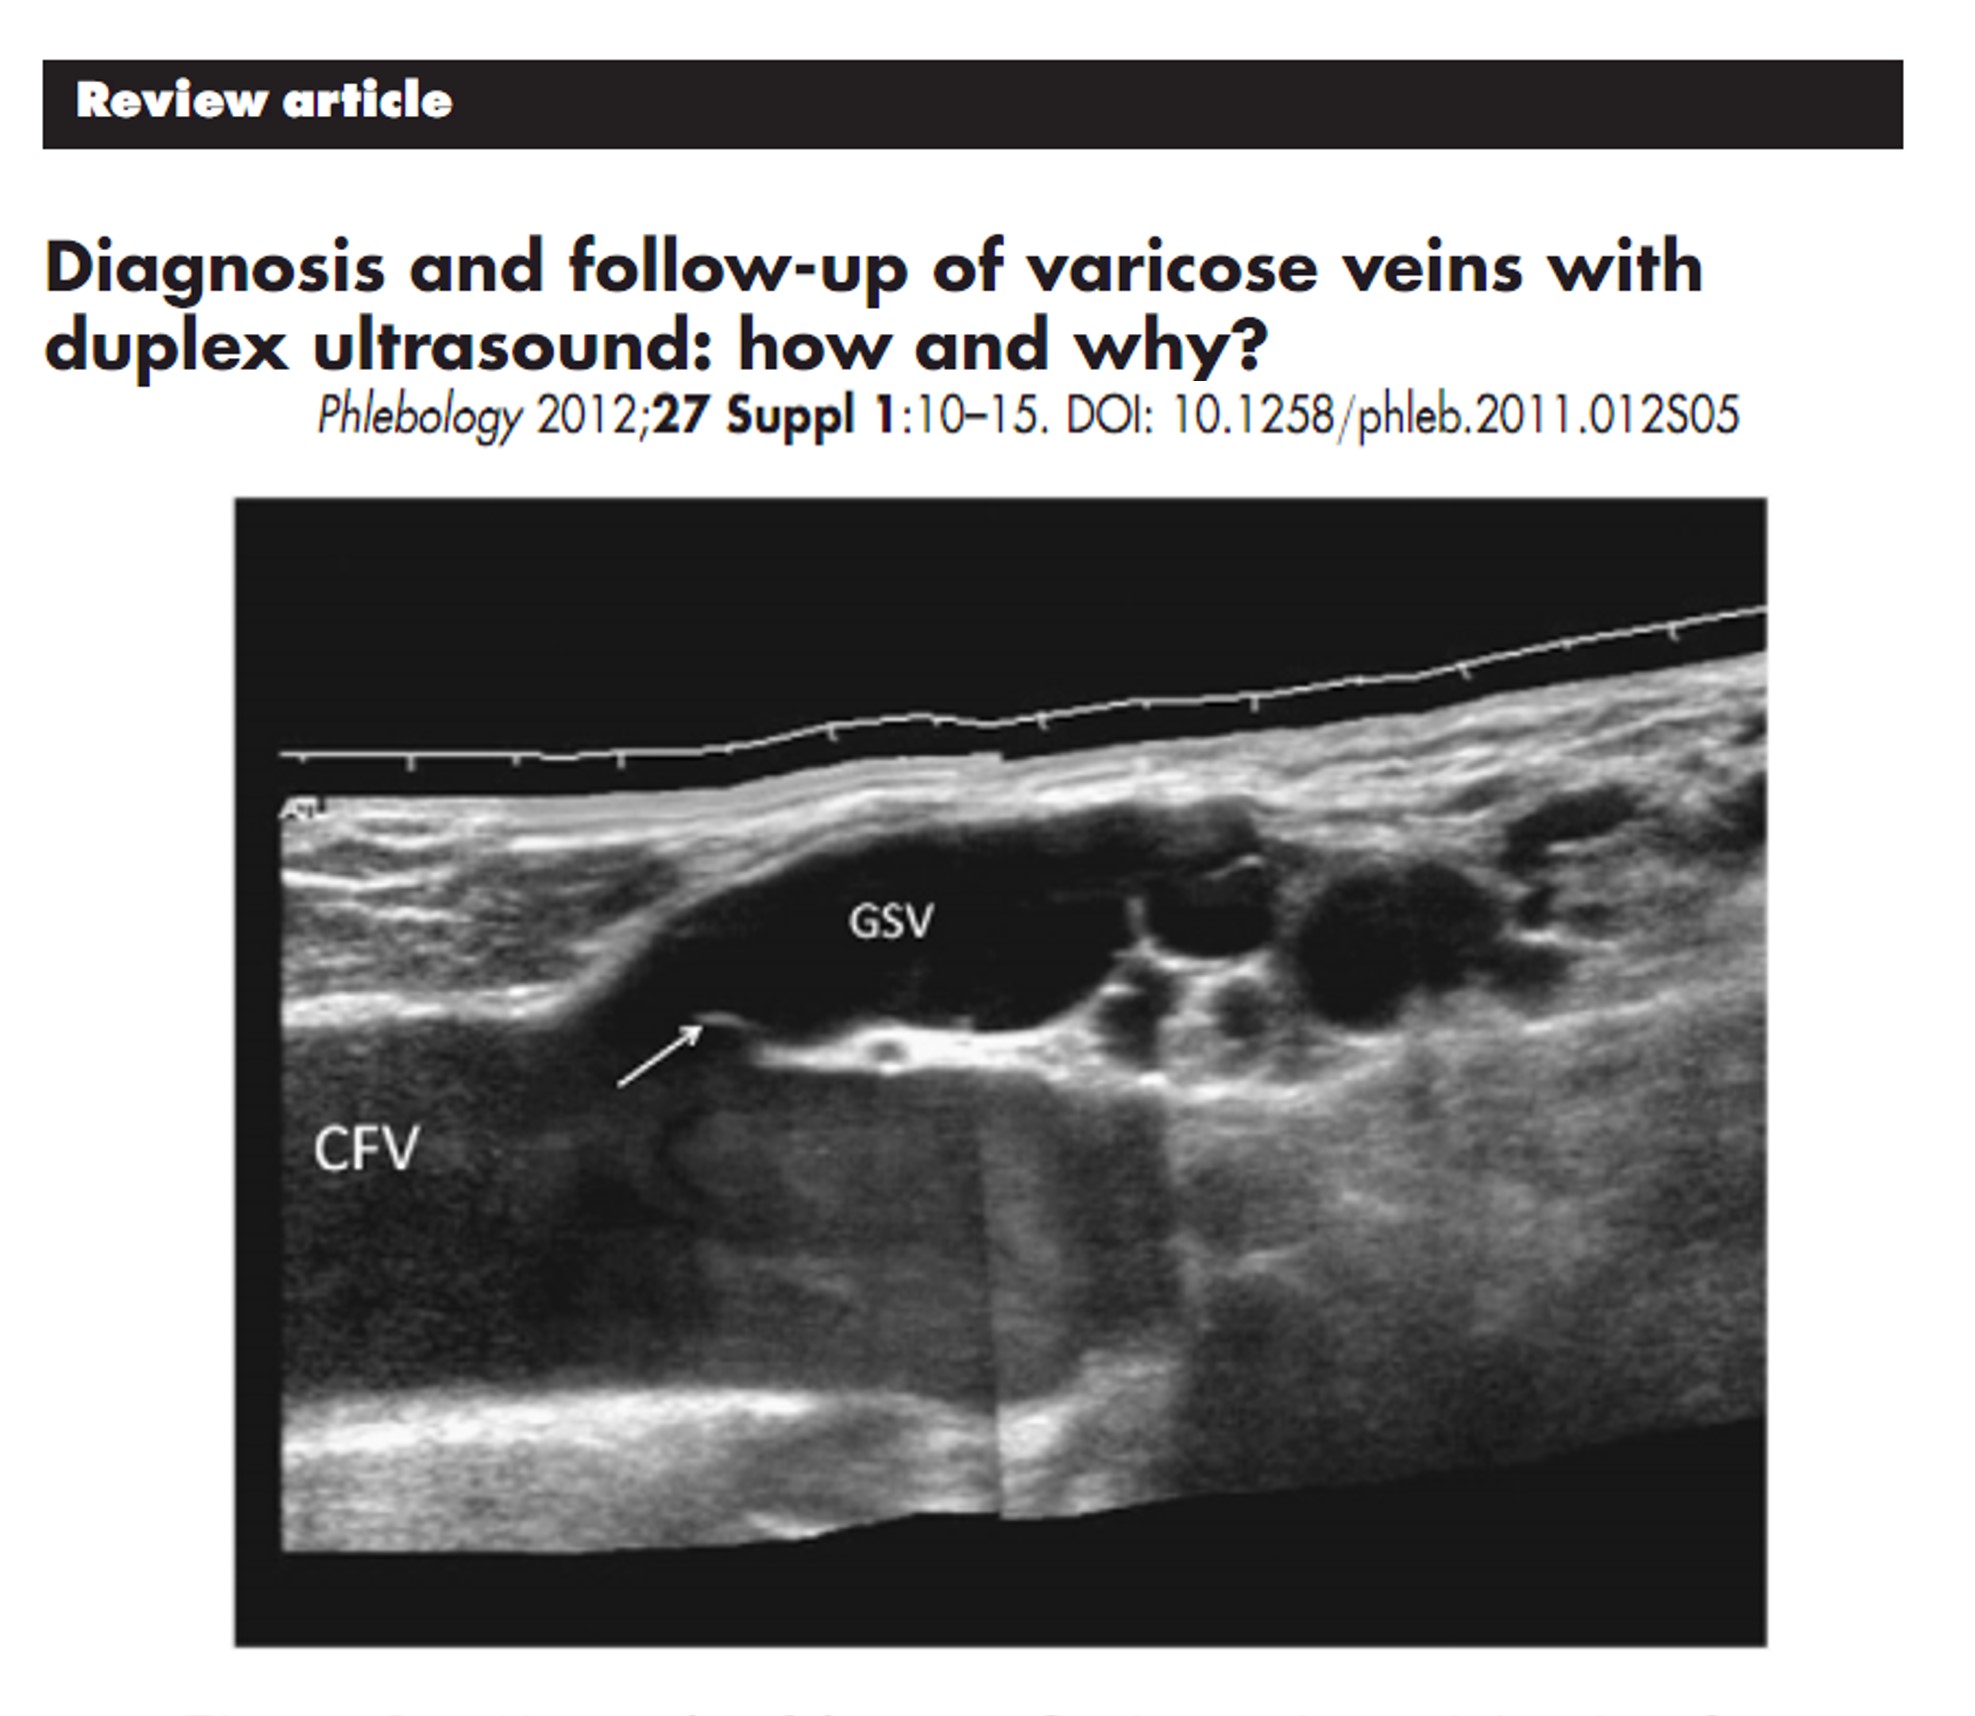

위의 논문에 나온 사진 GSV 우측에 보면

동글동글한 혈관이 바로 발거술 후 생긴 신생혈관이다

불규칙하게 생성되고 메두사머리의 모양으로 관찰되어

serpentine하다고 표현을 통상적으로 한다